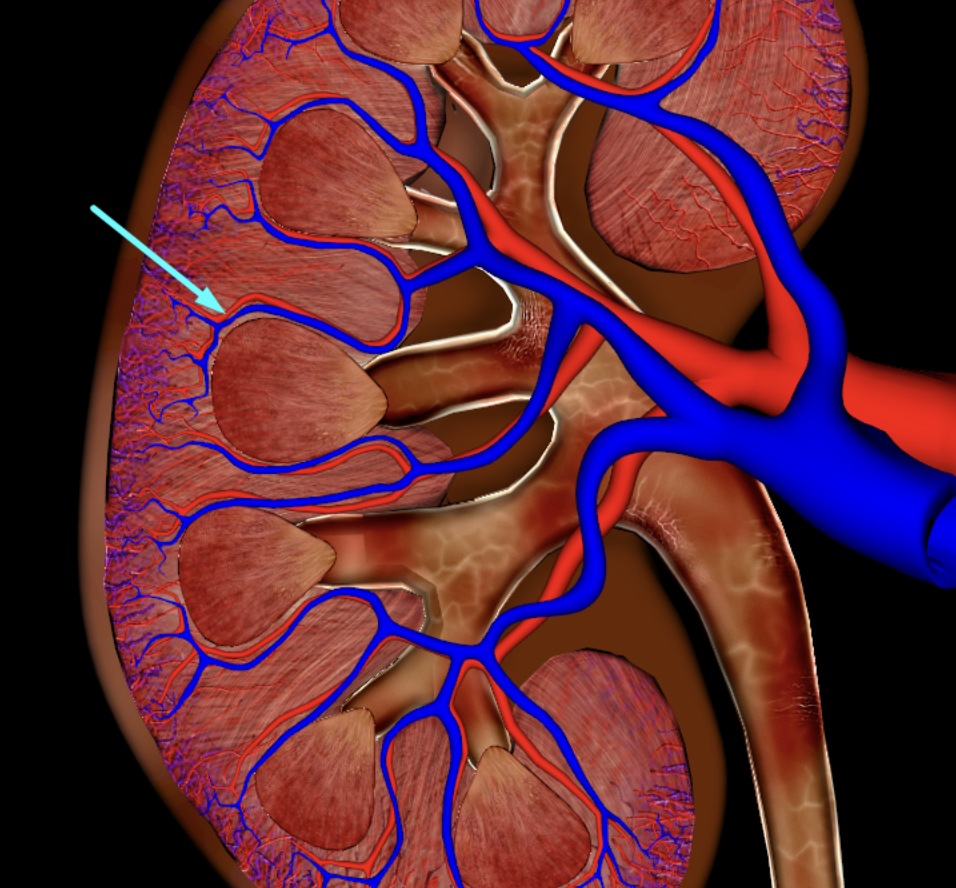

renal cortex

green

renal medulla

blue

renal columns

yellow

renal pyramids

purple

renal lobe

orange

renal papilla

minor calyx

teal

major calyces

renal pelvis

minor and major calyces